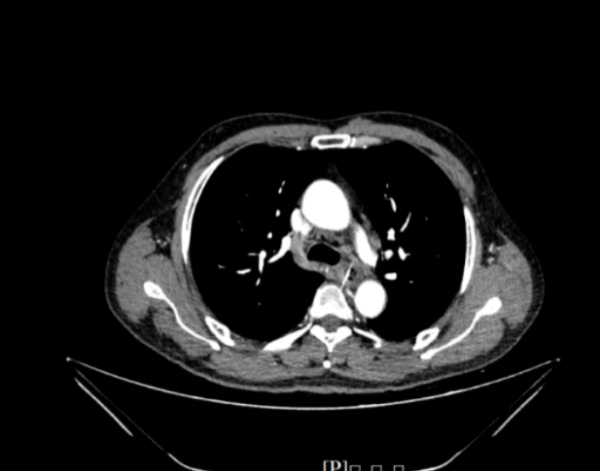

生命垂危之际,彭先生被紧急转运至南方医院,消化内科接诊后立即启动应急预案,巩兰波教授、赵芯梅教授、韩泽民医生医疗组连夜集结,为患者进行全方位评估。精准影像显示,鱼刺与肺动脉之间仅有毫厘之隔,取出过程犹如“在万丈悬崖边行走”。